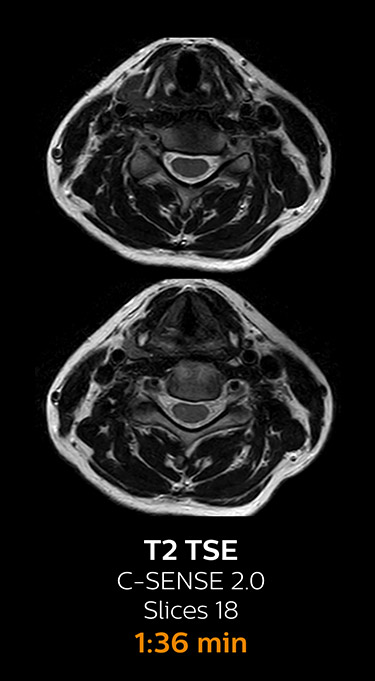

Fast MRI of cervical spine

With Compressed SENSE, the scan time for the routine cervical spine examination at KNC was reduced from 13:11 to 9:52 minutes, which corresponds to 25% reduction.

MRI examination of the cervical spine with Compressed SENSE

Ingenia 3.0T CX

Scan time 9:52 min. (was 13:11 min. without Compressed SENSE)